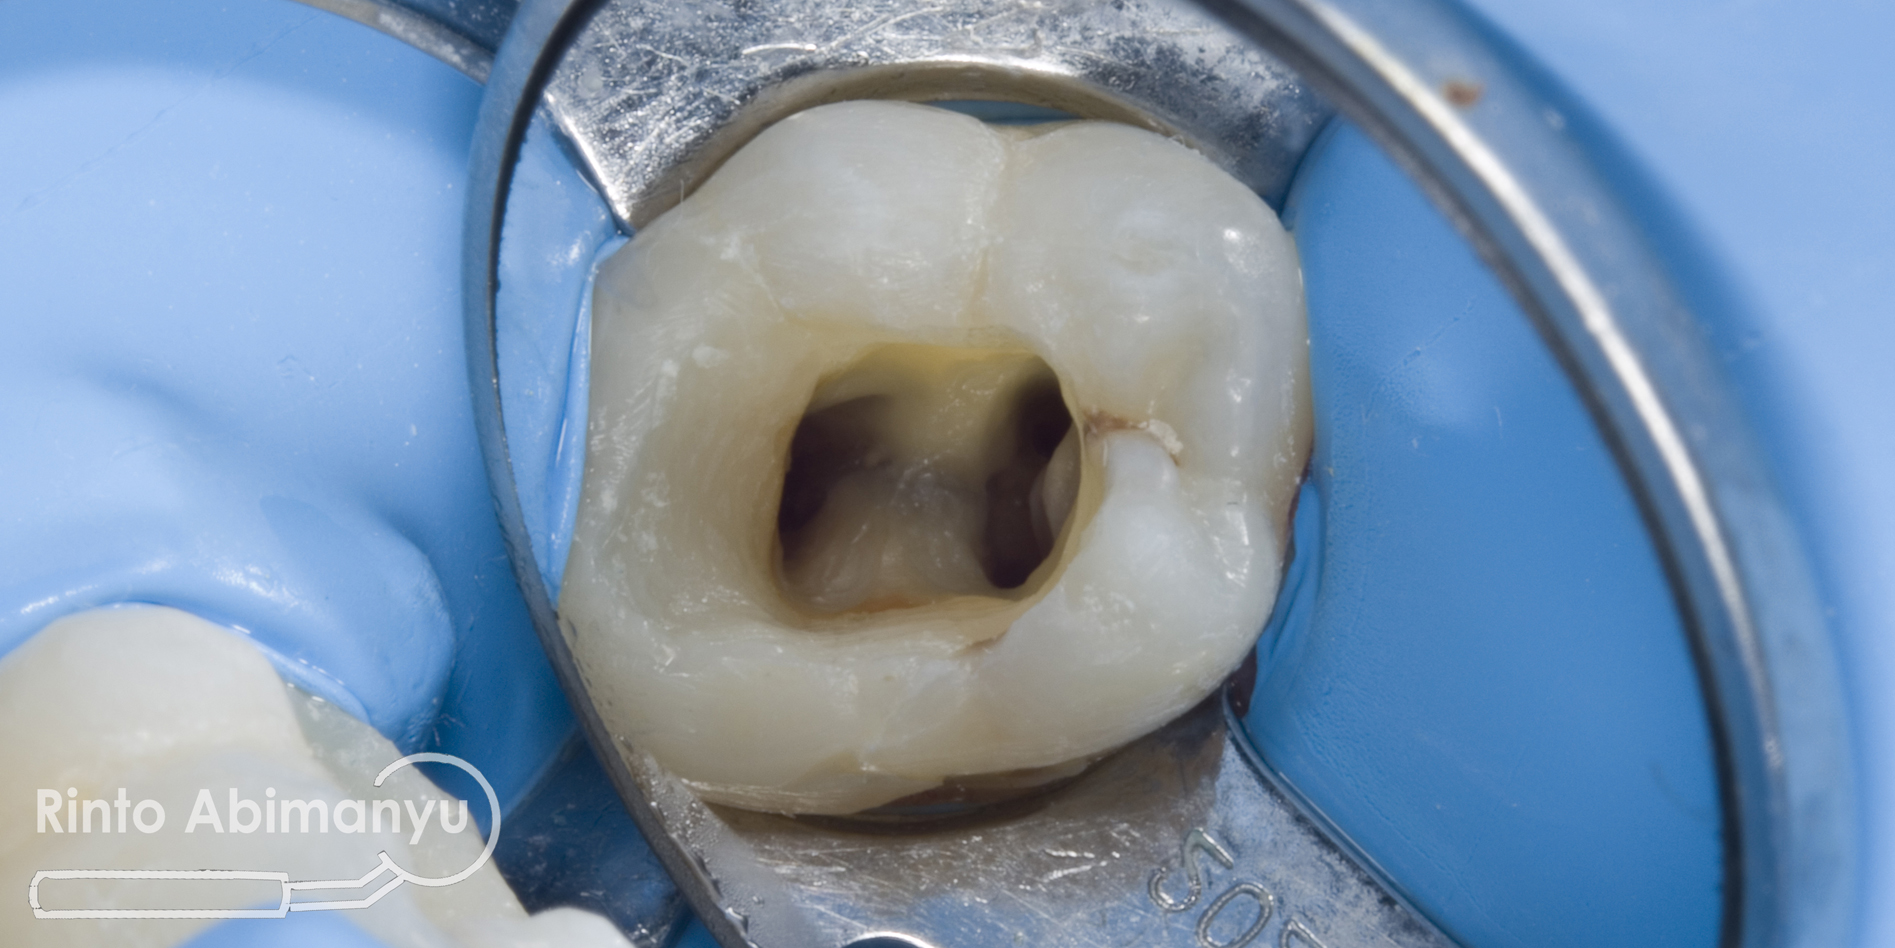

Seluruh jaringan karies dibuang menggunakan bur tungsten carbide low speed, dilanjutkan pembuatan artificial wall menggunakan komposit dengan bantuan matriks greatercurve.

Setelah artificial wall selesai dilakukan pemasangan rubberdam dan pembukaan kamar pulpa.. Untuk penjajakan awal digunakan K-File no.8 dilanjutkan no.10 terus sampai no. 20, ini dimaksudkan juga untuk mengamankan jalur luncur (secured the glide path) sebagai persiapan sebelum file rotari masuk…. Pengukuran panjang kerja menggunakan apex locator Root ZX mini (Morita)..